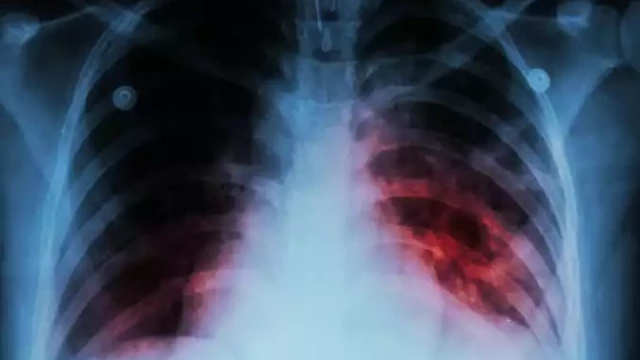

രാജ്യത്ത് ക്ഷയരോഗികളിൽ വർധന; 21.4 ലക്ഷം പുതിയ രോഗികൾ

ന്യൂഡൽഹി: രാജ്യത്ത് 21.4 ലക്ഷം പുതിയ ക്ഷയരോഗികൾ. 2021 ലെ കണക്കനുസരിച്ചാണിത്. ലോകാരോഗ്യ സംഘടനയുടെ ഗ്ലോബൽ ക്ഷയരോഗ റിപ്പോർട്ട് പ്രകാരം മുൻവർഷത്തേക്കാൾ 18 ശതമാനം വർധനവാണ് രോഗികളിൽ ഉണ്ടായിരിക്കുന്നത്. 22 കോടി ആളുകളെ പരിശോധനയ്ക്ക് വിധേയരാക്കി.